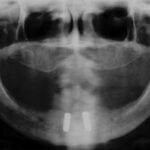

First-in-human 3D printed patient specific implant with polycaprolactone-tricalcium phosphate (PCL-TCP) microarchitecture for mandibular reconstruction.

First mandible reconstruction with Osteomesh shaped tray to hold autologous bone grafts. Bony ingrowth and remodeling observed at 2 and 5 months postoperatively.

First customized Osteopore (OSX) implant for orbital floor reconstruction.

The first in-human for mandible reconstruction took place.